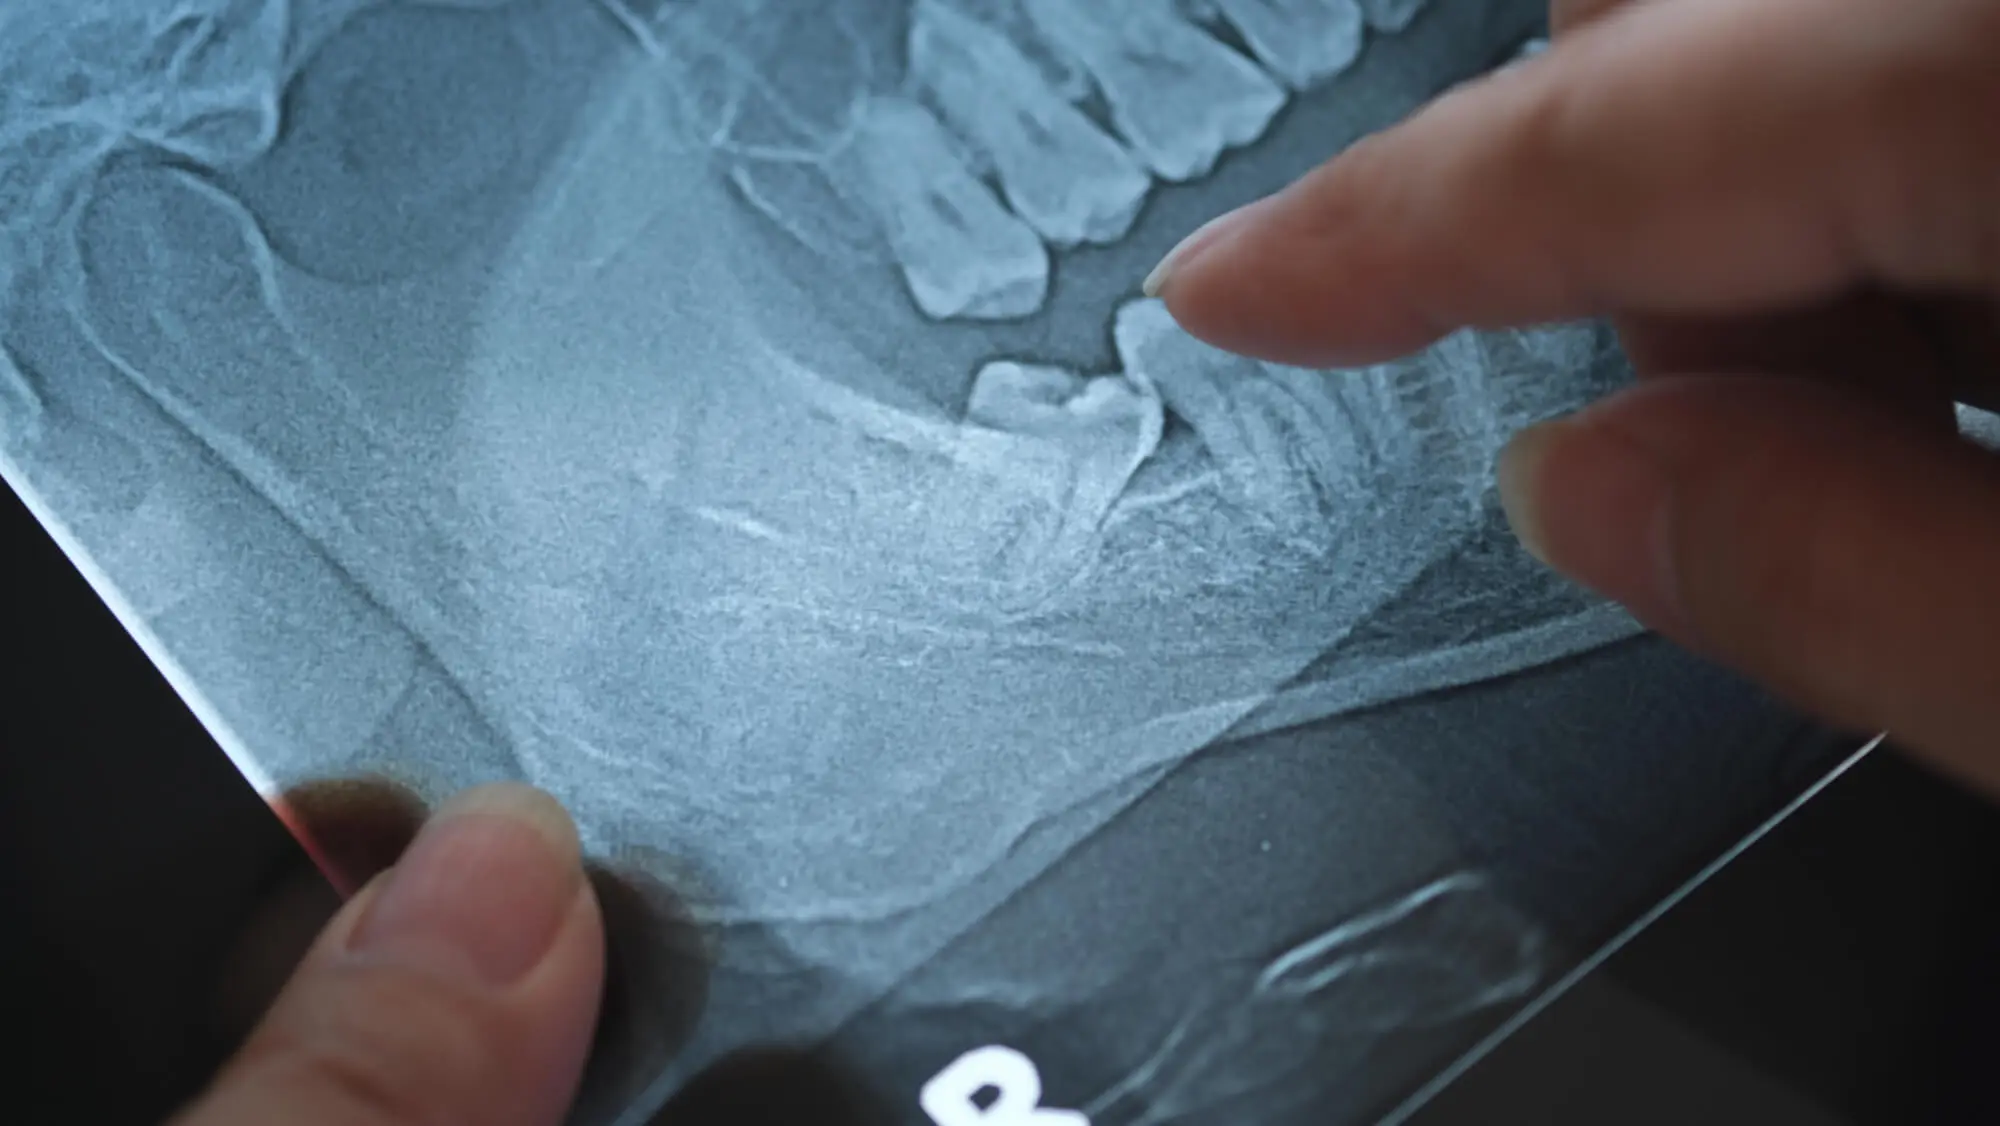

- X-ray Imaging: Helps assess impaction, alignment, and potential future problems.

There are different types of impactions (horizontal, vertical, and angular), and not all cause immediate symptoms. This makes regular dental checkups and close monitoring essential for growing mouths.